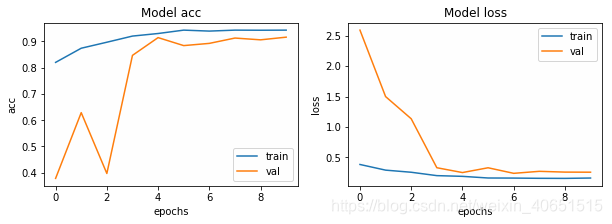

至此,模型已经构建好了,接下来,训练了10个迭代次数,批处理大小为32。(注意,通常批处理大小越大,效果越好,但是要以计算负担较大为代价。在该模型训练时,模型在第七次已经达到较好,Epoch 000015: ReduceLROnPlateau reducing learning rate to 9.000000427477062e-05.但是为了训练VGG快一点,只训练10次)大家在复现我的方法时,为了获得最佳结果,可以花费一些时间来进行超参数的调整。模型在迭代10次后其结果如下所示:

不同模型结果对比:

在该相同测试数据集上,迭代10次进行比较(其中VGG19模型内增加了各500个正负样本,调小了部分参数,便于训练):

| 深度学习模型 | P | R | F |

| 多层CNN | 86.96 | 90.35 | 83.89 |

| VGG19 | 89.76 | 96.66 | 93.08 |

在该数据集上现实,VGG19能够更好的进行肺炎疾病的检测。但是,VGG由于模型结构复杂,训练较慢,如果合作调整参数和增加数据集,应该会得到更好的效果。在这里我不在进行尝试。